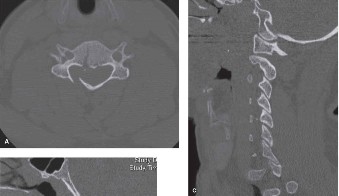

Pre-Operative Planning, Templating, and Patient Positioning

When surgical intervention becomes unavoidable, meticulous pre-operative planning is the cornerstone of a successful outcome. Advanced imaging is non-negotiable. An MRI with and without gadolinium contrast is the gold standard for defining the extent of the epidural abscess, the degree of neural compression, and the involvement of adjacent paraspinal musculature (e.g., psoas abscess). T1-weighted images typically show hypointense signals in the infected marrow, while T2-weighted and STIR sequences reveal hyperintense fluid and edema in the disc space and vertebral bodies. Gadolinium enhancement highlights the vascularized inflammatory phlegmon and the capsule of any abscesses.

In addition to MRI, a fine-cut computed tomography (CT) scan is essential for evaluating bony destruction. CT allows the surgeon to assess bone stock for pedicle screw purchase and to template the size of the interbody cages required for anterior column reconstruction. Upright standing radiographs (if the patient can tolerate them) or full-length supine films are necessary to evaluate global spinal alignment and regional kyphosis.